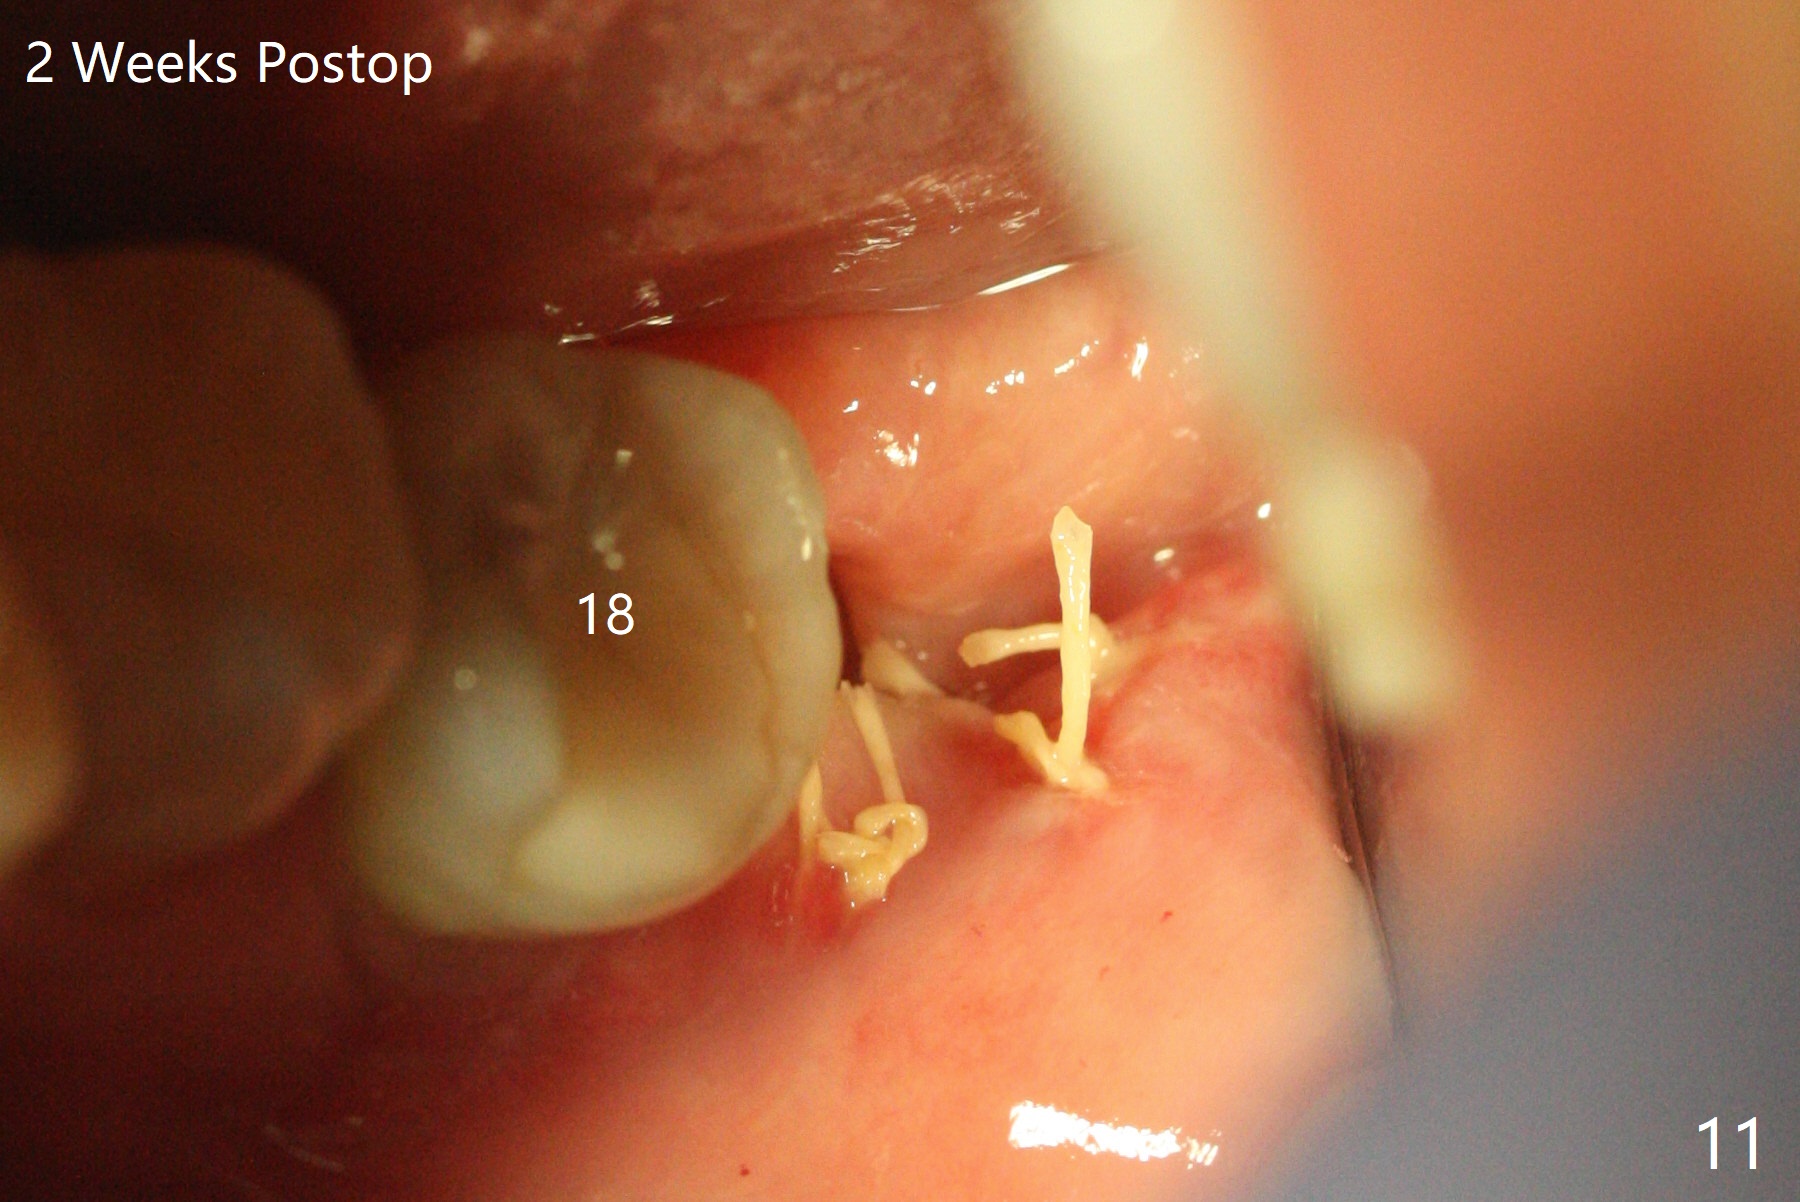

A 37-year-old woman requests extraction of the 3rd molars and orthodontic retreatment (Fig.1). Since the bone between #17 and 18 is thin and short (Fig.2 black *), bone graft is needed after #17 extraction. But the apical infection at #18 (Fig.2 white *) may affect graft survival. The patient agrees to have RCT retreatment done (Fig.3 white curved lines) before extraction (black area). The apical granulation tissue can be removed (Fig.4 red area) prior to bone graft (Augma). The latter will be also placed at #17 as a control. After endodontic consultation, the patient does not want RCT retreatment. She would like to have the 3rd molars extracted first and #18 removed if needed. After #17 extraction (Fig.5), apicoectomy will be performed at #18 (Fig.6 (white outline: surgical bur, use non-torque handpiece)). Following curettage of the apical lesion at #18 (Fig.7), bone graft will be placed (Fig.8 red circles). In fact the patient insists upon #1, 16, 17, and 32 extraction. After extraction, allograft (Fig.9 A (Ossogen, Mineralized Cort/Can (30%/70%), .25-1.0 mm) is placed in the mesioapical of the sockets of #17 and 32, while Osteogen Plug (O) and BioXclude in the distocoronal one (4-0 PGA suture). There is minimal bone between the 2nd and 3rd molars (black arrowheads). The allograft is intentionally pushed into #18 apical defect after enucleation (white arrowhead). The sockets are slightly open, although sutures are in place 2 weeks postop (Fig.10,11). It is unknown whether the bone graft is partially dislodged or not.